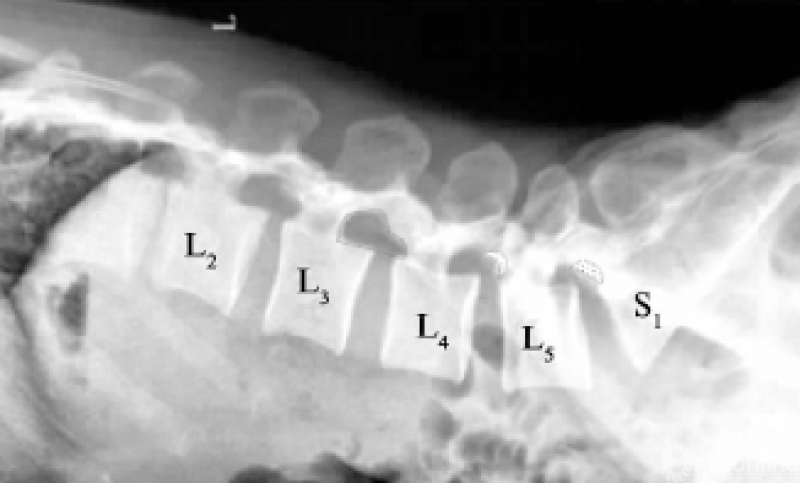

腰椎椎间孔形态与Kambin's三角空间密切相关,而Kambin's三角空间大,工作通道置管时则相对容易,安全系数高,反之则易损伤出口神经根。腰椎椎间孔呈上宽下窄的耳朵状,一般情况下孔的高度在腰椎各节段中相差不大,约20mm[25];L2/3椎间孔的上下径最大,越往下越小(见图5)。而孔的宽度或者厚度,一般由L1/2至L5S1递增,在L5S1中可达约19.8mm[25],这与腰关节突关节面由矢状位向冠状位变化有关。

L3/4以上节段椎间孔相对宽大,如图中虚线“耳朵状”;L4/5及L5S1节段椎间孔相对狭小,“半月形”轮廓为切除上关节突范围示意图

图5 34岁男性腰椎侧位X线片